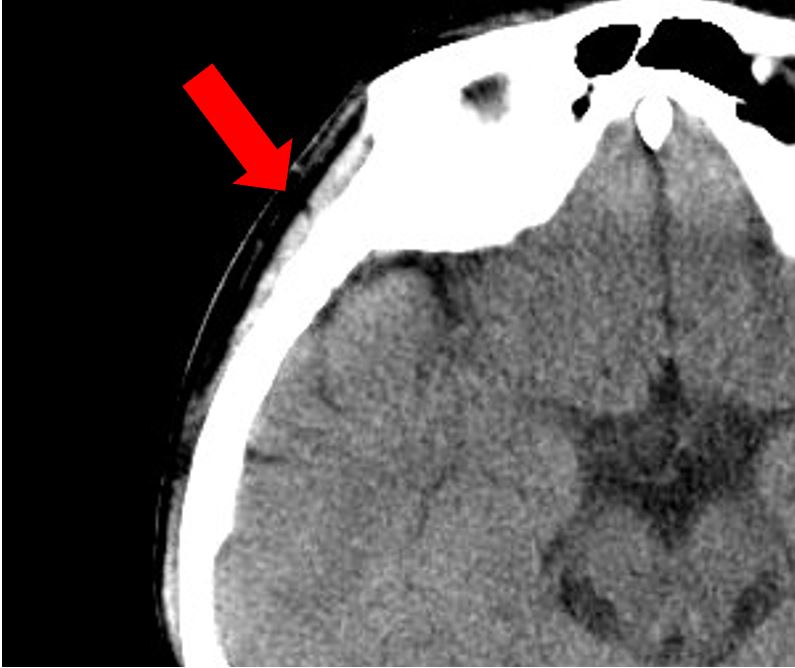

中脳レベルの画像で、側頭部に白い骨の外に薄くグレーに見えるのが側頭筋(矢印)です。

この側頭筋の厚さは、全身の骨格筋量や握力との相関が認められています。

筋力や栄養状態のアセスメントに活用できるので、脳画像を撮っている場合には、是非、チェックしてみてください。